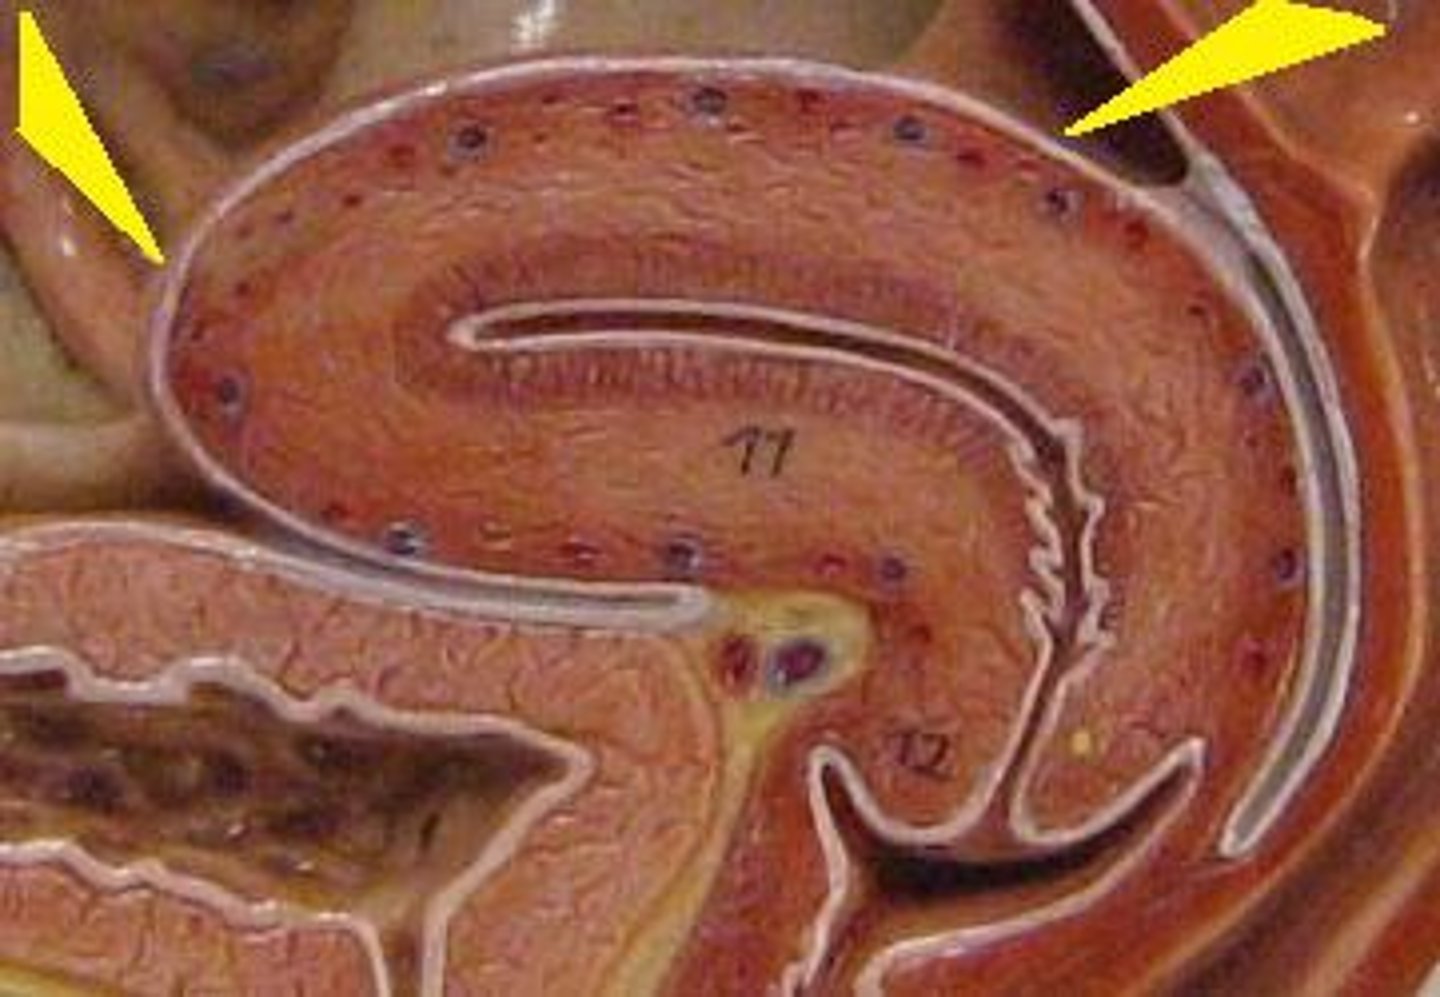

corpus luteum

8

early corpus luteum

9

late corpus luteum

10

corpus albicans

11

granulosa cells

12

theca cells

13

antrum

14